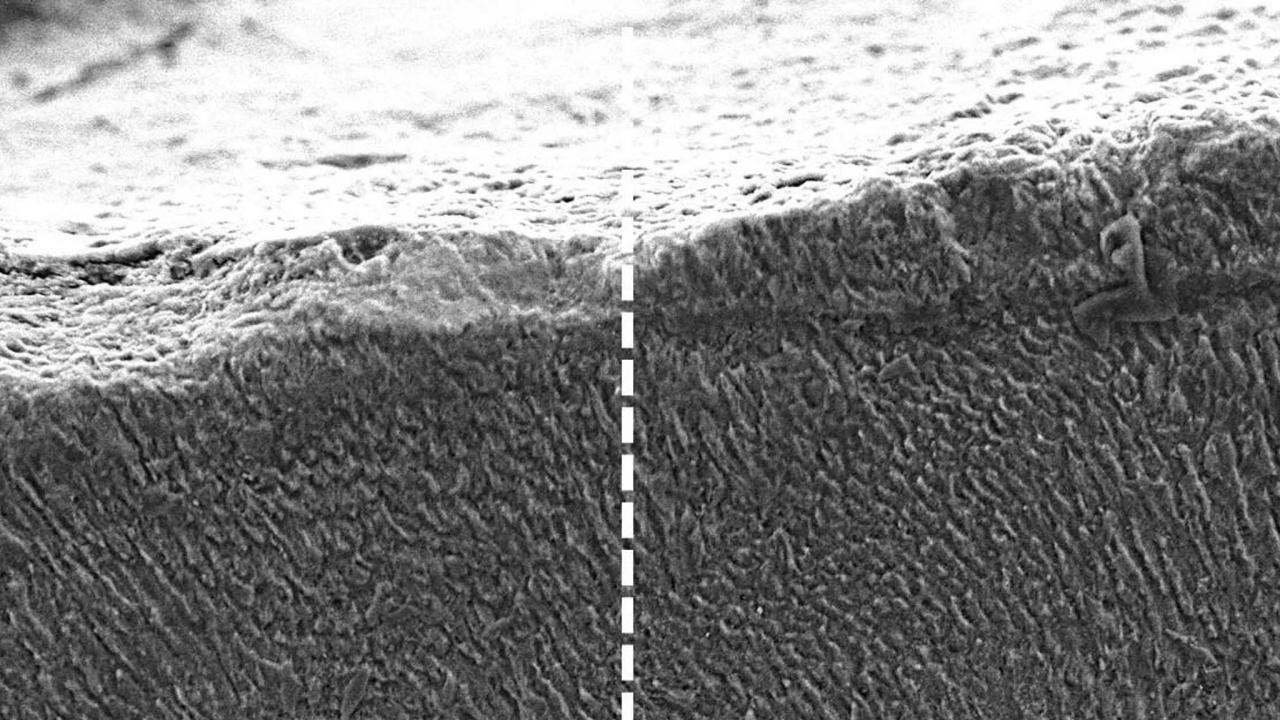

مينا الأسنان قبل وبعد علاج الكيراتين

من المعروف أن مينا الأسنان لا تتجدد بمجرد تلفها، وهو ما يجعل الاكتشاف الجديد واعدا للغاية. فبينما يقتصر دور الفلورايد في معاجين الأسنان والمياه على إبطاء تآكل المينا، أظهرت التجارب أن الكيراتين يمكنه إيقاف التآكل تماما، بل والمساعدة في استعادة المينا نفسها.